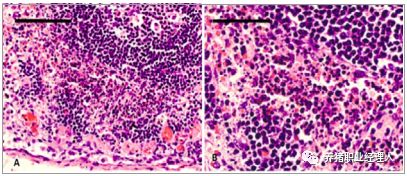

全身多个脏器淤血、出血、坏死是 ASF 的主要临床表现,大体病变见(临床诊断部分)。组织病理学表现为出血、淤血,脾脏(图19)、肝脏(图20)、胸腺(图21)、肠道(图22)、肺和脑(图23)等组织中的单核、淋巴细胞出现核固缩、核碎裂。鉴于ASF的特殊性,需要依靠病原学和血清学进行确诊和鉴别诊断。

图 19:ASFV 感染猪的脾脏(A、B)和扁桃体(C、D)。测方法 靶位基因 内参 敏感度 (拷贝数) A. 脾脏红髓和白髓大面积出血、坏死,淋巴细胞减少; B. 残存的淋巴组织(箭头所指);C-D. 淋巴细胞坏死、核碎裂。( 长箭头指部分隐窝,短箭头指部分滤泡)。来源:(Ganowiak, 2012)

图 22:急性 ASF 肠系膜淋巴结。淋巴细胞坏死、核碎裂。来源:(Ganowiak, 2012)